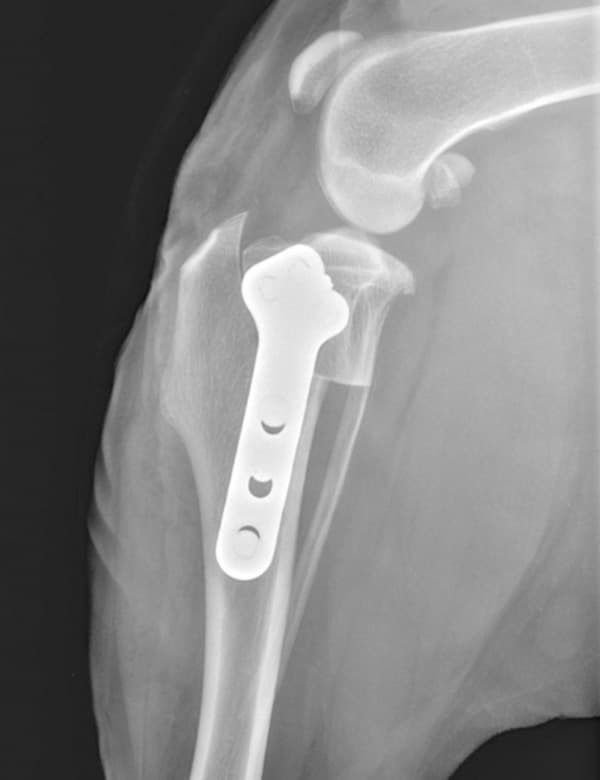

A Tibial Plateau Leveling Osteotomy is performed to treat cranial cruciate ligament (CCL) tears, one of the most common orthopedic injuries in dogs. Rather than repairing the ligament directly, this surgery changes the angle of the tibial plateau (the top of the shinbone) to stabilize the knee and prevent abnormal forward motion. Our doctors will examine your pet and discuss whether TPLO surgery is the most appropriate option. Tibial Plateau Leveling Osteotomy (TPLO)